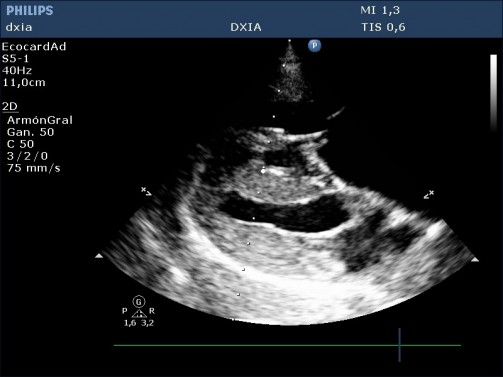

Predominancia de cámaras derecha, con marcada dilatación de estas (AD y VD)

Hipertrofia moderada de pared libre del VD y del SIV

No aplanamiento septal